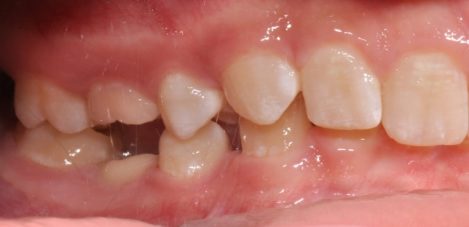

Problems in the treatment of ankylosing deciduous molars

Анкилозата на зъб се определя като анатомично сливане на алвеоларна кост с цимента на зъбния корен.Този феномен може да се появи по време на пробив на зъба или след това.